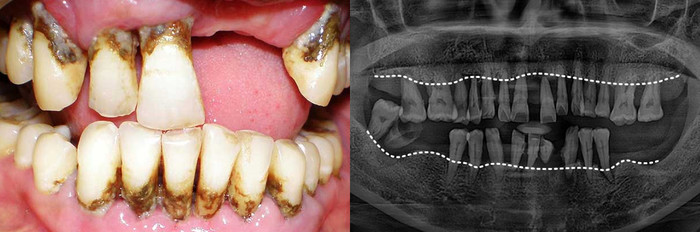

치주질환 그대로 방치한다면

잇몸뼈까지 소실됩니다

치주질환을 방치하면 뼈가 녹아내리며, 결국 발치에 이르게 됩니다.

잇몸이 무너진 후 치료는 더욱 어렵습니다.

겉으로 보기에도 치석과 염증이 심하며, 잇몸이 심하게 붓고 내려앉아 있습니다. 엑스레이에서는 뿌리의 절반 이상이 드러날 정도로 잇몸뼈가 심각하게 소실되어 있습니다.